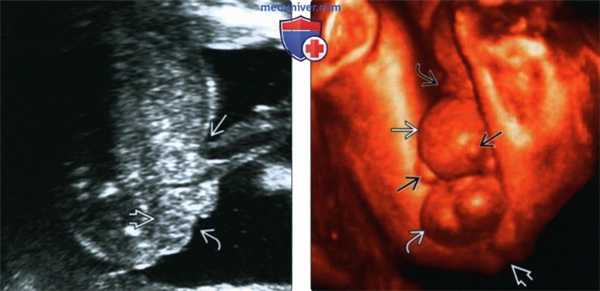

(Справа) МРТ плода с дефектом в нижней части передней брюшной стенки и отсутствием мочевого пузыря и анальной ямки по данным УЗИ, поперечная плоскость. Пуповина прикреплена к омфалоцеле, расположенному в верхней части дефекта. Кроме того, визуализируется только одна почка. (Слева) МРТ того же плода, Т1-ВИ, средняя сагиттальная плоскость. Подтверждается частичное выпадение печени. В толстой кишке визуализируется гиперинтенсивный меконий, однако в пресакральном пространстве сигнал отсутствует, что свидетельствует об отсутствии прямой кишки.

(Справа) МРТ того же плода, Т2-ВИ, сагиттальная плоскость. Через дефект передней брюшной стенки также выпадают петли толстой кишки. Подтверждается прикрепление пуповины к омфалоцеле, образующему верхнюю часть дефекта. Такое сочетание находок характерно для клоакальной экстрофии. «Отсутствующая» почка визуализируется в малом тазу.